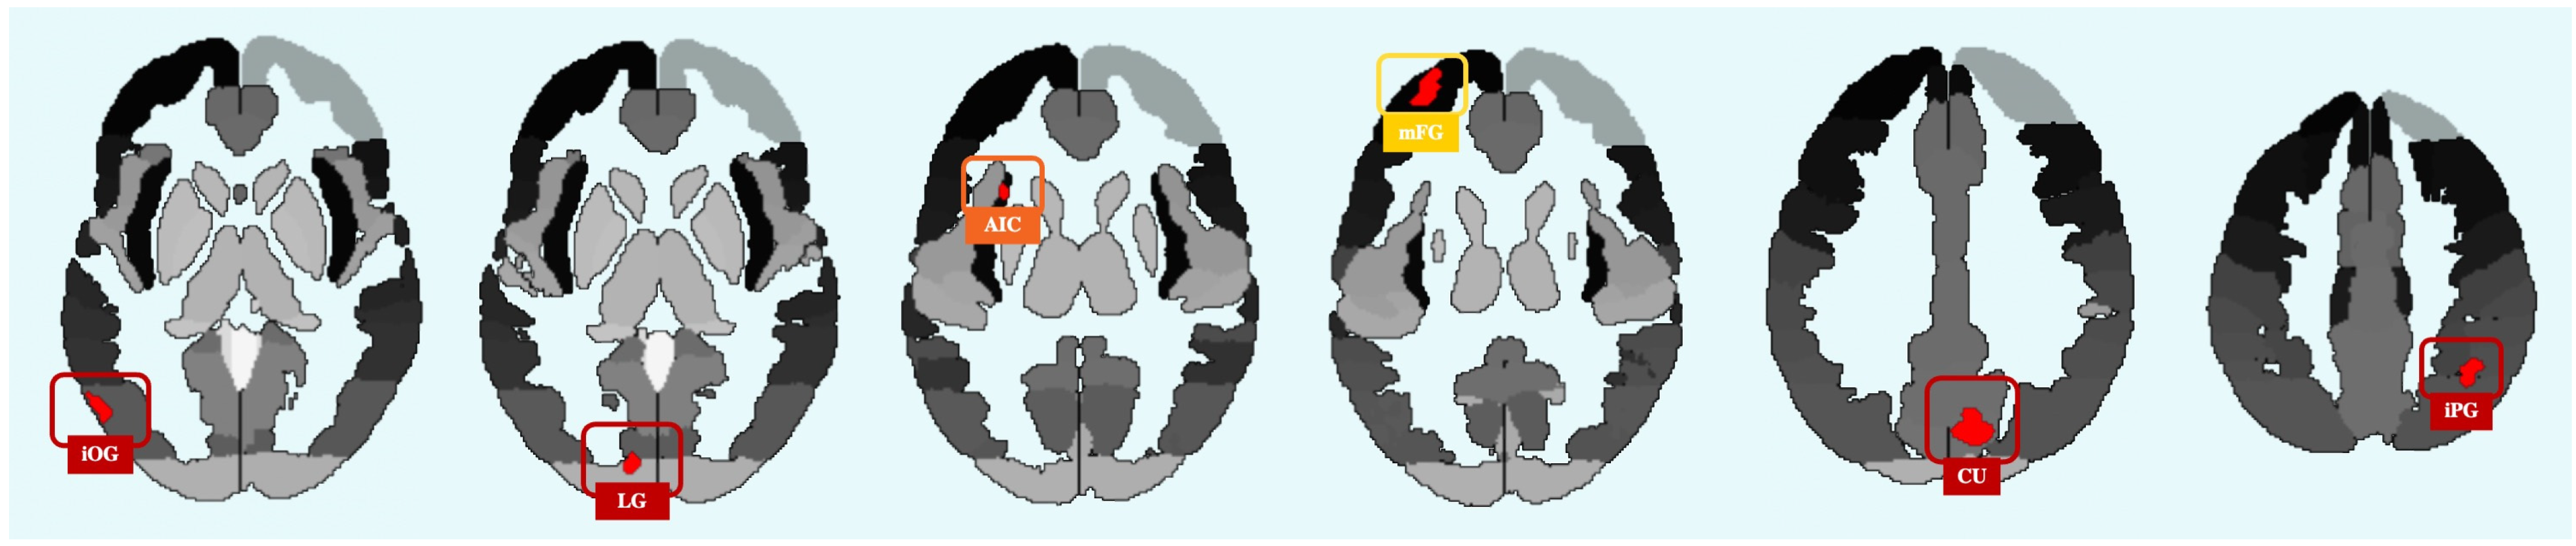

| H | Peak Region | MNI Coordinates | Voxel No. | BSR | |||

|---|---|---|---|---|---|---|---|

| Young > Old | x | y | z | ||||

| R | Cuneus | +10 | −78 | +32 | 641 | 0.000000 | |

| L | Middle Frontal Gyrus | −28 | +58 | +12 | 109 | 0.000000 | |

| L | Lingual Gyrus | −18 | −84 | −16 | 98 | 0.000001 | |

| L | Inferior Occipital Gyrus | −54 | −72 | −2 | 79 | 0.000010 | |

| L | Anterior Insular Cortex | −28 | +14 | +12 | 76 | 0.000010 | |

| R | Inferior Parietal Gyrus | +38 | −52 | +42 | 70 | 0.000040 | |